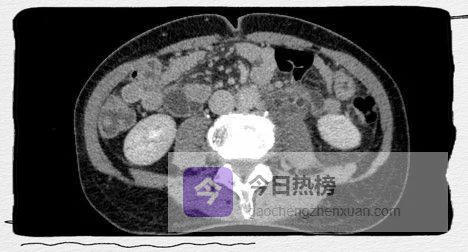

图2A

CT增强扫描呈双环及双腔改变,早期可见外腔密度增高。